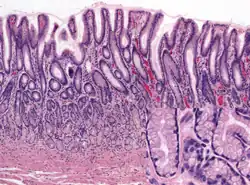

Microanatomy

Wall

Like the other parts of the gastrointestinal wall, the human stomach wall from inner to outer, consists of a mucosa, submucosa, muscular layer, subserosa and serosa.[19]

The inner part of the stomach wall is the gastric mucosa a mucous membrane that forms the lining of the stomach. The membrane consists of an outer layer of columnar epithelium, a lamina propria, and a thin layer of smooth muscle called the muscularis mucosa. Beneath the mucosa lies the submucosa, consisting of fibrous connective tissue.[20] Meissner's plexus is in this layer interior to the oblique muscle layer.[21]

Outside of the submucosa lies the muscular layer. It consists of three layers of muscular fibres, with fibres lying at angles to each other. These are the inner oblique, middle circular, and outer longitudinal layers.[22] The presence of the inner oblique layer is distinct from other parts of the gastrointestinal tract, which do not possess this layer.[23] The stomach contains the thickest muscular layer consisting of three layers, thus maximum peristalsis occurs here.

Glands

The mucosa lining the stomach is lined with gastric pits, which receive gastric juice, secreted by between 2 and 7 gastric glands. Gastric juice is an acidic fluid containing hydrochloric acid and digestive enzymes.[24] The glands contains a number of cells, with the function of the glands changing depending on their position within the stomach.

Within the body and fundus of the stomach lie the fundic glands. In general, these glands are lined by column-shaped cells that secrete a protective layer of mucus and bicarbonate. Additional cells present include parietal cells that secrete hydrochloric acid and intrinsic factor, chief cells that secrete pepsinogen (this is a precursor to pepsin- the highly acidic environment converts the pepsinogen to pepsin), and neuroendocrine cells that secrete serotonin.[25]

Glands differ where the stomach meets the esophagus and near the pylorus.[26] Near the gastroesophageal junction lie cardiac glands, which primarily secrete mucus.[25] They are fewer in number than the other gastric glands and are more shallowly positioned in the mucosa. There are two kinds - either simple tubular glands with short ducts or compound racemose resembling the duodenal Brunner's glands. Near the pylorus lie pyloric glands located in the antrum of the pylorus. They secrete mucus, as well as gastrin produced by their G cells.[27]